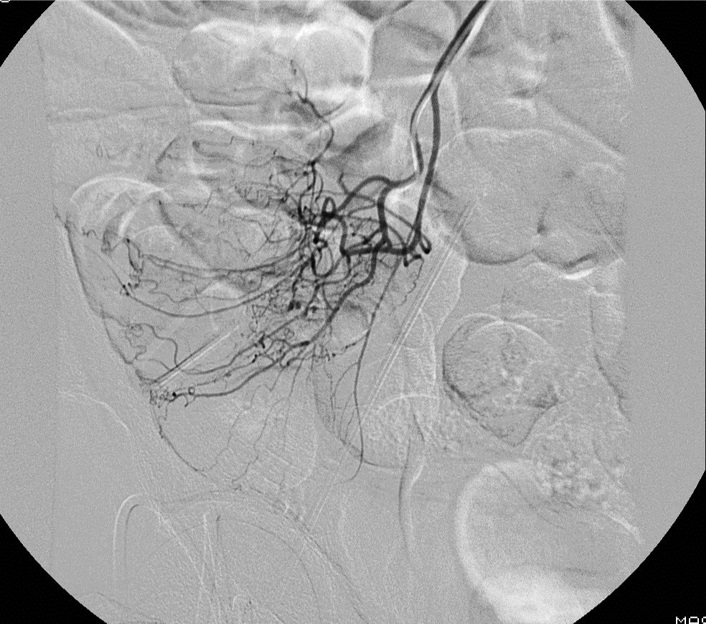

病例二:结肠憩室急性大出血(微导管接近出血)

64岁 男性 无相关病史。因下消化道出血急诊室就诊。考虑到急诊出血情况下效果差,未进行结肠镜检查。CTA 未显示造影剂外溢,但右结肠/回肠大憩室。临床持续出血和生命体征恶化,介入医生会诊决定进行动脉造影。

造影剂外溢